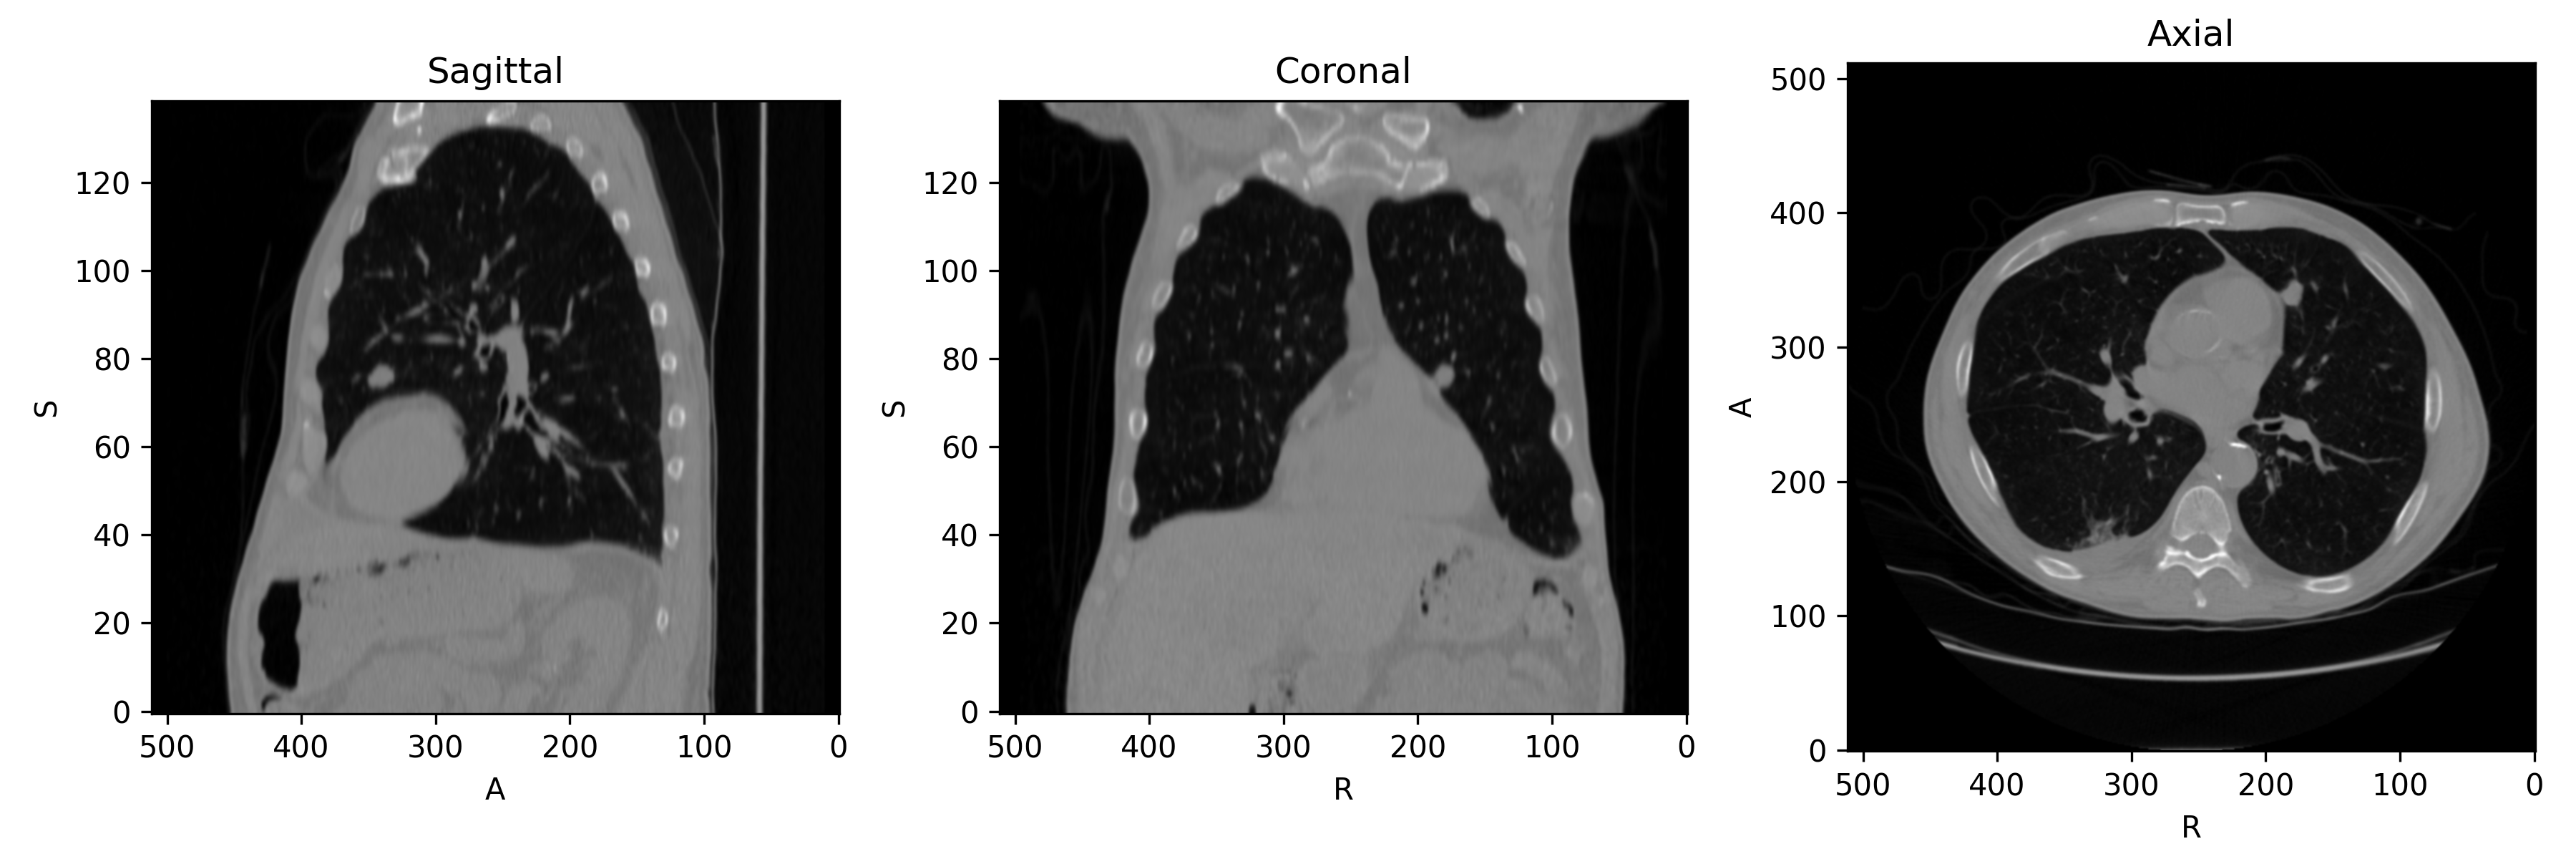

First, let's get a 3D chest CT we can use for demonstration. The plotted slices intersect a lung nodule near the heart.

The image looks like this: